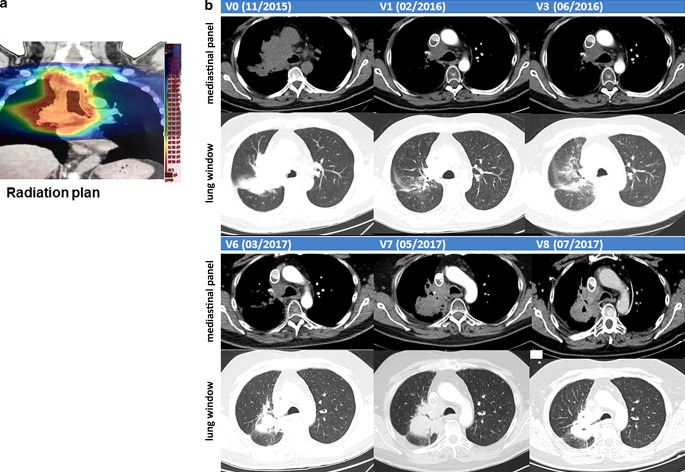

Fig. 2.

a Radiation plan. b Representative computed tomograpgy (CT) scans (upper panel: mediastinal window; lower panel: lung window) before and after therapies (V0–V8): lung at diagnosis (V0, 11/2015), after RCT (V1, 2/2016), after NK cell therapy (V3, 3/2016), after pseudo-tumor progress (V6, 3/2017), after 3 injections of nivolumab treatment (V7, 5/2017), and 20 months after diagnosis without tumor progression (V8, 7/2017)

A 58-year-old male patient was diagnosed with histologically proven, inoperable, stage IIIb squamous NSCLC (cT4, cN3, cM0; Karnofsky >90%) in 11/2015 (V0; Fig. 1). A mHsp70-positive tumor phenotype (V0) was confirmed by elevated exosomal Hsp70 (exHsp70) serum levels (11 ± 2.4 ng/ml), as determined by the lipHsp70 ELISA [20]. The radiation plan (total dose: 64.8 Gy) is shown in Fig. 2a. H&E staining of a bronchoscopy at diagnosis (V0) revealed a typical tumor morphology with atypical mitoses (Fig. 3a). Following simultaneous RCT, a partial tumor response was assessed after 3 months by CT scanning (V1, Fig. 2b). The RCT-induced decrease in tumor size was accompanied by a drop in exHsp70 concentrations (11 ± 2.4 ng/ml to 8 ± 2.3 ng/ml to 6 ± 1.1 ng/ml, V0–V2). The amount of free Hsp70, which predominantly originates from dying tumor cells (R&D ELISA), remained unaltered between V0 and V1, but gradually increased thereafter.

CT scanning after NK therapy (V3–V5) revealed no tumor progression 12 months after diagnosis (data not shown). As Hsp70 serum concentrations increased concomitantly with C‑reactive protein (CRP) between V2 and V4 (exHsp70: 22 ± 2.6 ng/ml), it was assumed that inflammation rather than tumor growth caused this increase. Sixteen months after diagnosis (V6), a higher cell density was detected by CT scanning in the previously irradiated area of the right upper lobe of the lung (Fig. 2b). Since tumor progression was assumed based on CT scanning, the patient received nivolumab as a second-line therapy in a non-metastatic setting. However, 18 months after diagnosis (V7), IHC analysis of a CT-guided bronchoscopy revealed no signs of viable tumor cells, but fibrotic tissue which is indicative of a pseudo-progress (V7, Fig. 3b). We hypothesize that the massive infiltration of CD56+ NK and CD3+ T cells detected inside the tumor (V7) which was absent at diagnosis (V0, Fig. 4) was responsible for the increased cell density determined by CT scanning at V6. In the follow-up, no tumor progression (V8, Fig. 2b) and no distant metastasis were detectable by CT scanning 33 months after diagnosis.